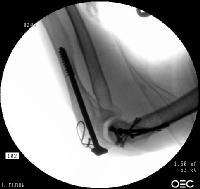

Screws were secured from the central articular component to the more proximal humeral cortices.

Click for larger image

These provided biplanar fixation, eventually with two screws in each direction.

The lateral column was then secured with two cannulated screws.